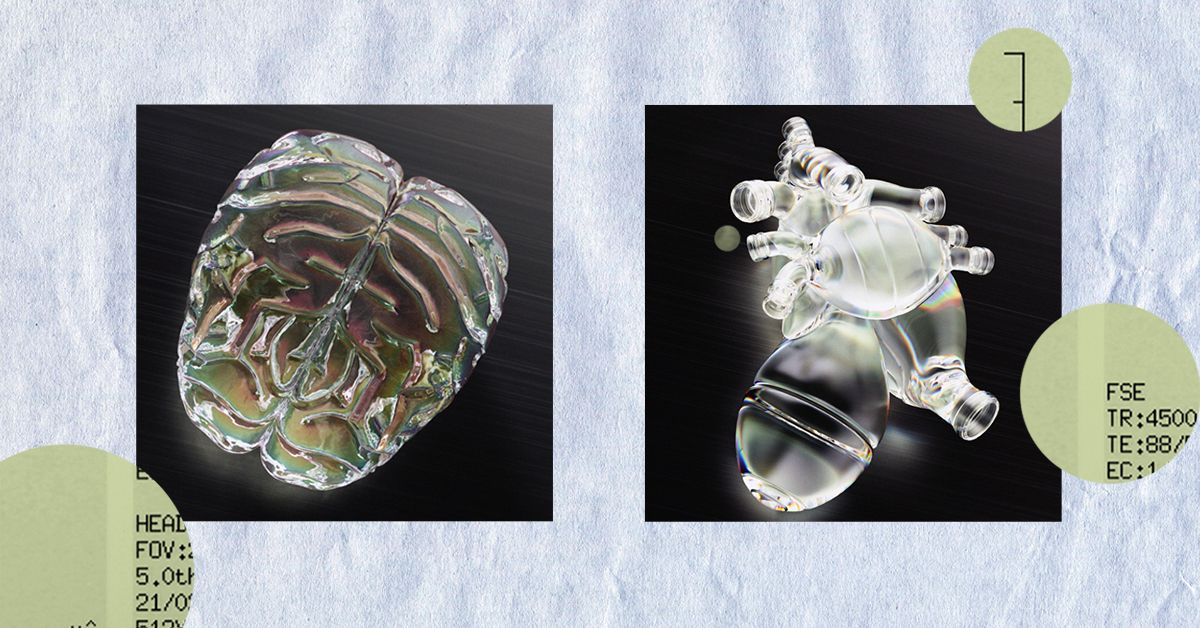

קיים קשר ידוע בין מחלת אלצהיימר למחלות לב וכלי דם. מחקרים קודמים מראים שייתכן שיש קשר גנטי בין שני המצבים

במחקר עוקבה פרוספקטיבי שפורסם לאחרונה ב The Lancet Regional Health – אירופהחוקרים מהולנד חקרו את הסיכונים לסיבוכי רבייה לאחר זיהומים